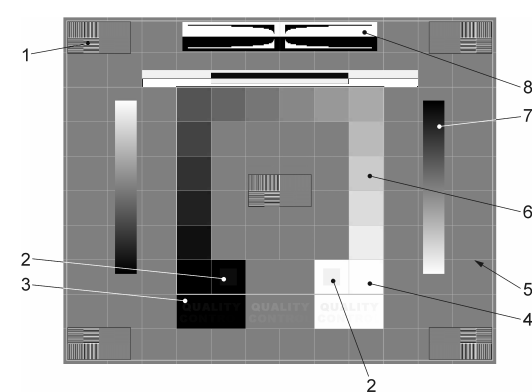

9.9. Constancy check

-

Test criteria (The numbers refer to the test pattern elements from DIN 6868-157).

-

Hide the form mask. This can be recalled at any time (tap on the test image shows button with check mark).

-

Select the criterion with the check mark if the condition is fulfilled.

-

Save the execution and its results.

-

Get more information (opens the manual, see following section).

The figure shows the individual test pattern elements. The following points must be checked in detail (according to the standard):

-

Visibility of the line pair grids with high CONTRAST in the middle and in the four corners of the TEST IMAGE (test pattern element 1)?

-

Visibility of the 5 % and 95 % fields (test pattern element 2)?

-

Quality control:

-

In the white and grey field:"QUALITY CONTROL" for all room classes

-

In the black field:

-

Mammography:"QUALITY CONTROL".

-

RK1 (? 50 lx):"QUALITY CONTRO".

-

RK2 (? 100 lx):"QUALITY CONT".

-

RK3 (? 500 lx):"QUALITY CON" (test pattern element 3)?

-

-

-

Visibility of the borders and lines of the raster and the centering of the raster in the active area of the Display (test pattern element 5)?

-

Continuity of the appearance of the gradient bars (test pattern element 7)?